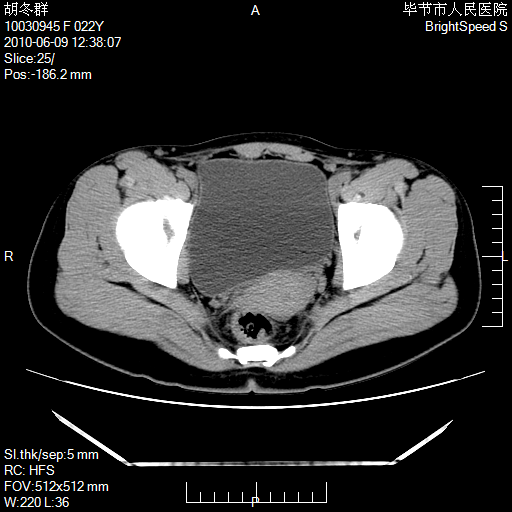

患者23岁,发现腹部包块3月。

盆腔内囊性占位;穿刺或者直接手术拿掉即可,不必紧张。

盆腔内囊性占位性病变;考虑左侧卵巢囊腺瘤。

有分隔、壁薄,支持考虑左侧卵巢囊腺瘤。

左侧卵巢浆液性囊腺瘤。

有分隔、壁薄,支持考虑左侧卵巢囊腺瘤。排尿后,膀胱缩小,由于重力作用,肿块下移就到了膀胱位置,很好理解。